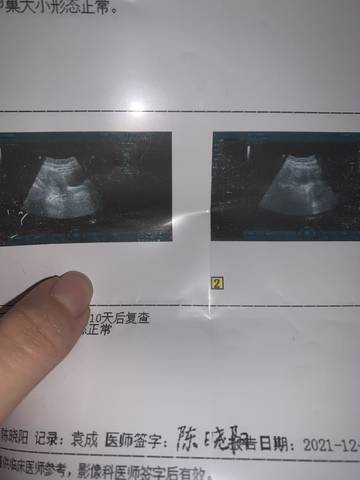

孕7周 HCG变成7000 孕酮变成1.8 从B超来看是不是已经自然流出来 而且第一次B超就没有发现孕囊 没有发育起来 医生让我住院药流

journal_insert_pic_1677938022journal_insert_pic_1677938029

#我正在参加,超级妈妈大赛赢奖品#这个数值这么低,基本上就是胎停了 听医生的建议,住院药流 放宽心,宝宝还会来的

这种这么低的数值的话,基本上就可以确定孩子已经胎停了,而且是应该是已经就是排出来了,所以说身体数值才这么低。